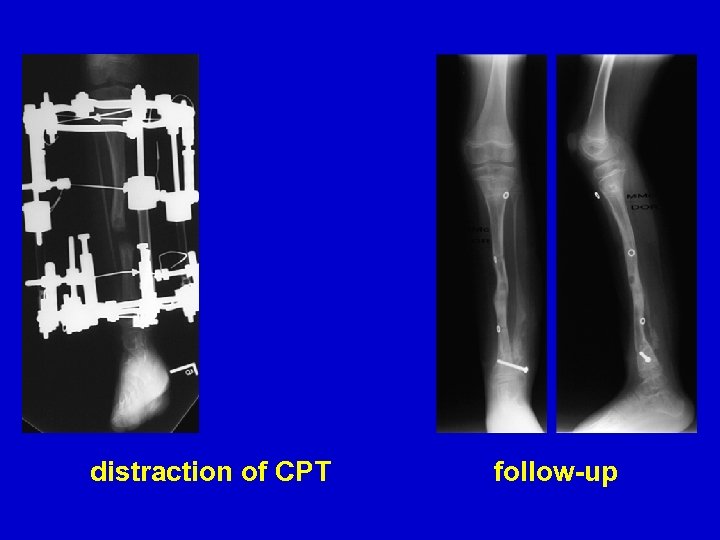

distraction of CPT follow-up

distraction of CPT follow-up